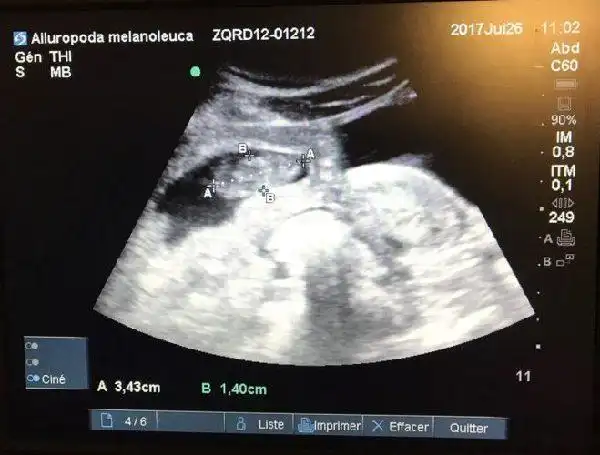

旅法大熊猫欢欢怀上双胞胎生产日期临近图

7月26日做的b超检查证实欢欢怀孕了,胚胎长3.4厘米.